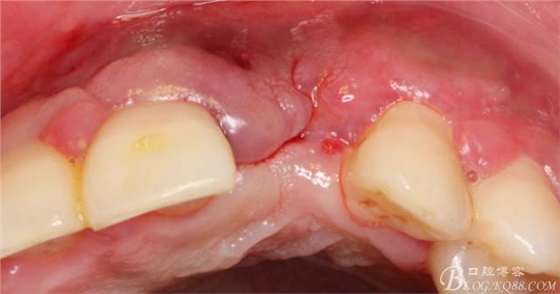

10天拆線一切正常,又過(guò)了兩周患者復(fù)診,自述期間無(wú)異常??趦?nèi)檢查,真的嚇了一跳,唇側(cè)鼓了個(gè)包,擠壓有白色分泌物溢出,絕對(duì)不是膿液,液體排除后,術(shù)區(qū)觸診空虛,外觀塌陷。這時(shí)候考研大夫的時(shí)刻到了,是先觀察一段時(shí)間再說(shuō)?還是馬上進(jìn)行處理?我的回答是:馬上處理!如果你沒(méi)有及時(shí)處理,而是放患者回家觀察,那么接下來(lái)會(huì)發(fā)生如下情況:1.回家后患者家屬及親友會(huì)有很多你可以想象得到的討論;2.患者及家屬會(huì)對(duì)你產(chǎn)生不信任,勢(shì)必會(huì)到其他門(mén)診或醫(yī)院檢查,他院大夫會(huì)不會(huì)發(fā)表對(duì)你不利的言論;3甚至?xí)蚁嚓P(guān)法律界人士找你討要說(shuō)法。

于是我果斷告知患者,手術(shù)失敗了,不能拖延,如不及時(shí)處理,炎癥繼續(xù)發(fā)展會(huì)很快波及鄰牙牙槽骨?;颊呓邮芪业慕ㄗh。切開(kāi)翻瓣,骨粉及生物膜消失了,骨吸收嚴(yán)重,幸運(yùn)的是,因?yàn)樘幚砑皶r(shí),鄰牙骨支持依然存在。